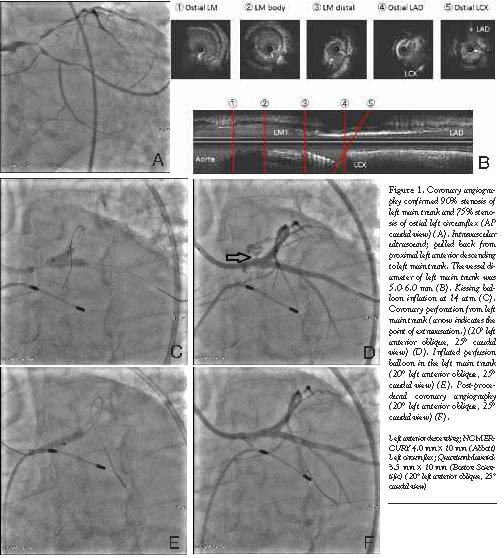

Case Report. A 77-year-old male was admitted for acute interstitial pneumonitis and gastric cancer. The patient developed chest discomfort during the hospital stay. His coronary artery multi-detector computed tomography examination revealed a significant LMT lesion. His echocardiography showed diffuse hypokinesia with depressed systolic function, and ejection fraction was 40%. Following the test, the chest discomfort worsened further and was accompanied by diffuse ST-depression on electrocardiogram. At the same time, the blood pressure fell down from 120 mm Hg to 100 mm Hg. Coronary artery bypass graft was considered, but deferred because the patient was still on high-dose steroids for interstitial pneumonitis and had significant bilateral carotid artery stenosis and gastric cancer. The decision was made to proceed to PCI with bare metal stents. Coronary angiography confirmed the distal LMT trifurcation lesion with heavy calcification (Figure 1A).

The procedure was performed under intra-aortic balloon pump support. An 8 Fr JL4.0 guiding catheter was engaged, and rotational atherectomy was performed for LMT-left anterior descending (LAD) lesion with a 1.75 mm and a 2.15 mm burr. Then the LMT-left circumflex (LCX) lesion was also treated with a 1.75-mm burr. As he had elective total gastrectomy scheduled for his gastric cancer, we chose bare metal stents and underwent T stenting. From distal to ostial LCX, S-STENT (Biosensors) 3.0 x 18 mm and DRIVER 3.0 x 18 mm (Medtronic Medical) were placed. Intravascular ultrasound (IVUS) showed that the external elastic membrane diameter was 5.0-6.0 mm at the LMT (Figure 1B). Based on the IVUS findings, a S-STENT 3.5 x 14 mm was placed from LMT to LAD at 18 atm. Then, jailed LCX was recrossed and kissing balloon technique (KBT) was utilized with 2 non-compliant balloons [4.0 mm (LAD) and 3.5 mm (LCX)] at 14 atm (Figure 1C). The balloons were inflated for 10 seconds, and blood pressure did not change. After KBT, perforation of LMT was noted (Figure 1D). Sealing of the perforation was attempted immediately with a 4.0 mm balloon, which had been used for KBT. However, blood pressure fell under 80 mm Hg within 30 seconds. Thus, we switched to a perfusion balloon, and due to similar episode of hypotension, the balloon could be inflated for only 90 seconds. Surprisingly, repeat angiogram showed that hemostasis was achieved successfully (Figure 1F). After waiting for a few minutes, no effusion or clinically significant bleeding was noted. The patient was monitored in the coronary care unit for 2 days, and transferred back to pulmonary service uneventfully.